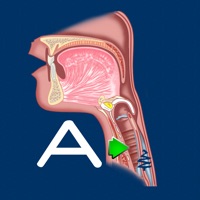

1. The Aspiration Disorders app helps students and patients learn and professionals teach aspiration swallowing disorders.

2. Animated anatomical illustrations, key disorder highlight and a MBS and FEES video for each view help patients and students learn.

3. • Animations for aspiration, silent and penetration and normal views.

5. The app features normal, aspiration, silent and penetration/cough views.

6. The Aspiration Disorders app makes learning swallowing disorders easy.